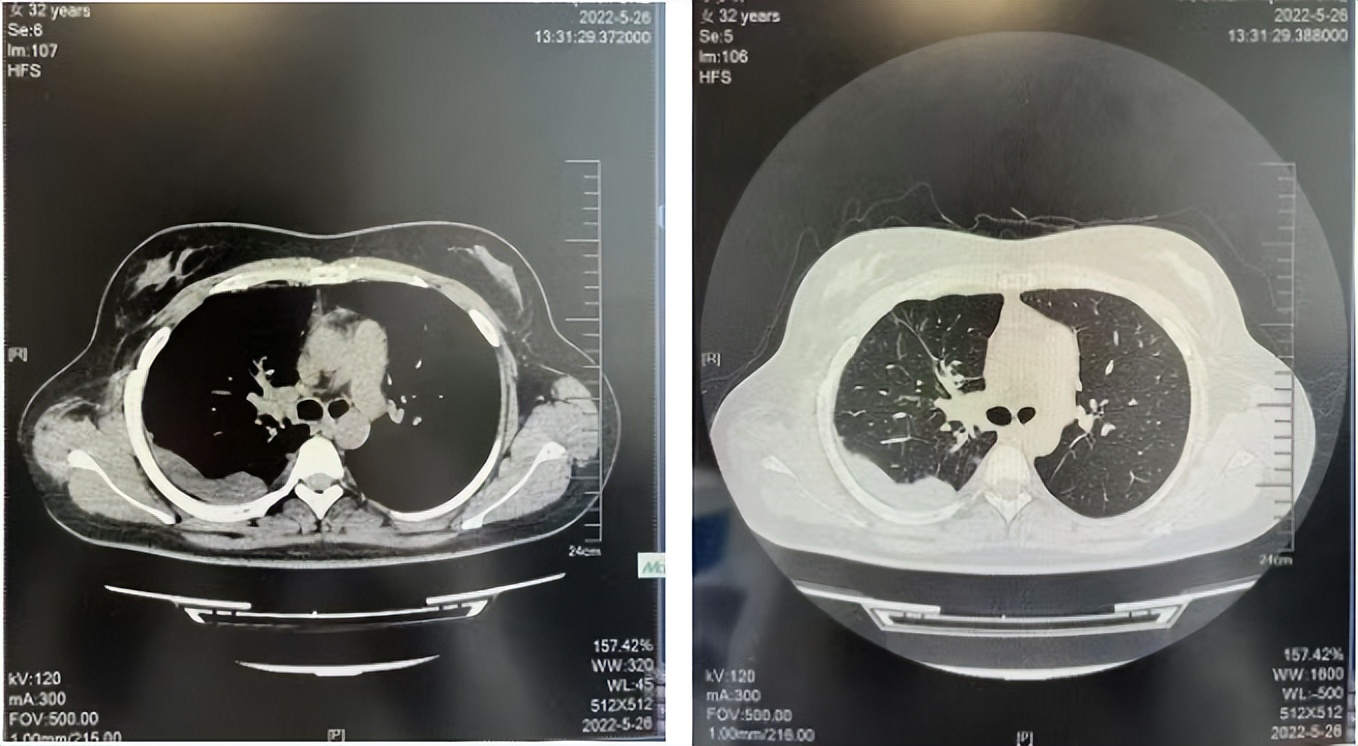

2016年1月复查CT提示支气管截断可见新发小结节,一线治疗采用培美曲塞+DDP方案化疗4周期(培美曲塞3.36,DDP 480mg)。化疗后复查胸部CT:右肺见不规则结节样影,最大层面大小约19mm*8mm,较前比较明显增大,疗效评估PD。2017.3-2017.4予单药多西他赛化疗3周期,疗效评估SD。2018年5月末复查CT提示结节较前增大,评效为PD,2018年6-10月予多西他赛+CBP化疗4周期,疗效评估SD。2022年5月患者出现活动后气短,复查胸部CT示右肺膨胀不良;右侧胸腔积液增多。胸腔积液包埋病理示符合肺腺癌细胞。行NGS基因检测:EML4:exon13-ALK:exon20融合。PD-L1(克隆号22C3)TPS<1%。

临床诊断:右肺上叶恶性肿瘤rT0N0M1a IVA期(第9版分期);恶性胸腔积液。

诊疗经过:2022年5月始口服克唑替尼3个月,出现肝功能异常(DILI 2级伴临床症状),改用恩沙替尼靶向治疗至今,目前评效为维持PR。恩沙替尼应用期间出现轻度肝功能异常(DILI 1级),对症处理后好转。截止目前PFS 33个月。

2018.07

2022.05

2022.08

2023.05